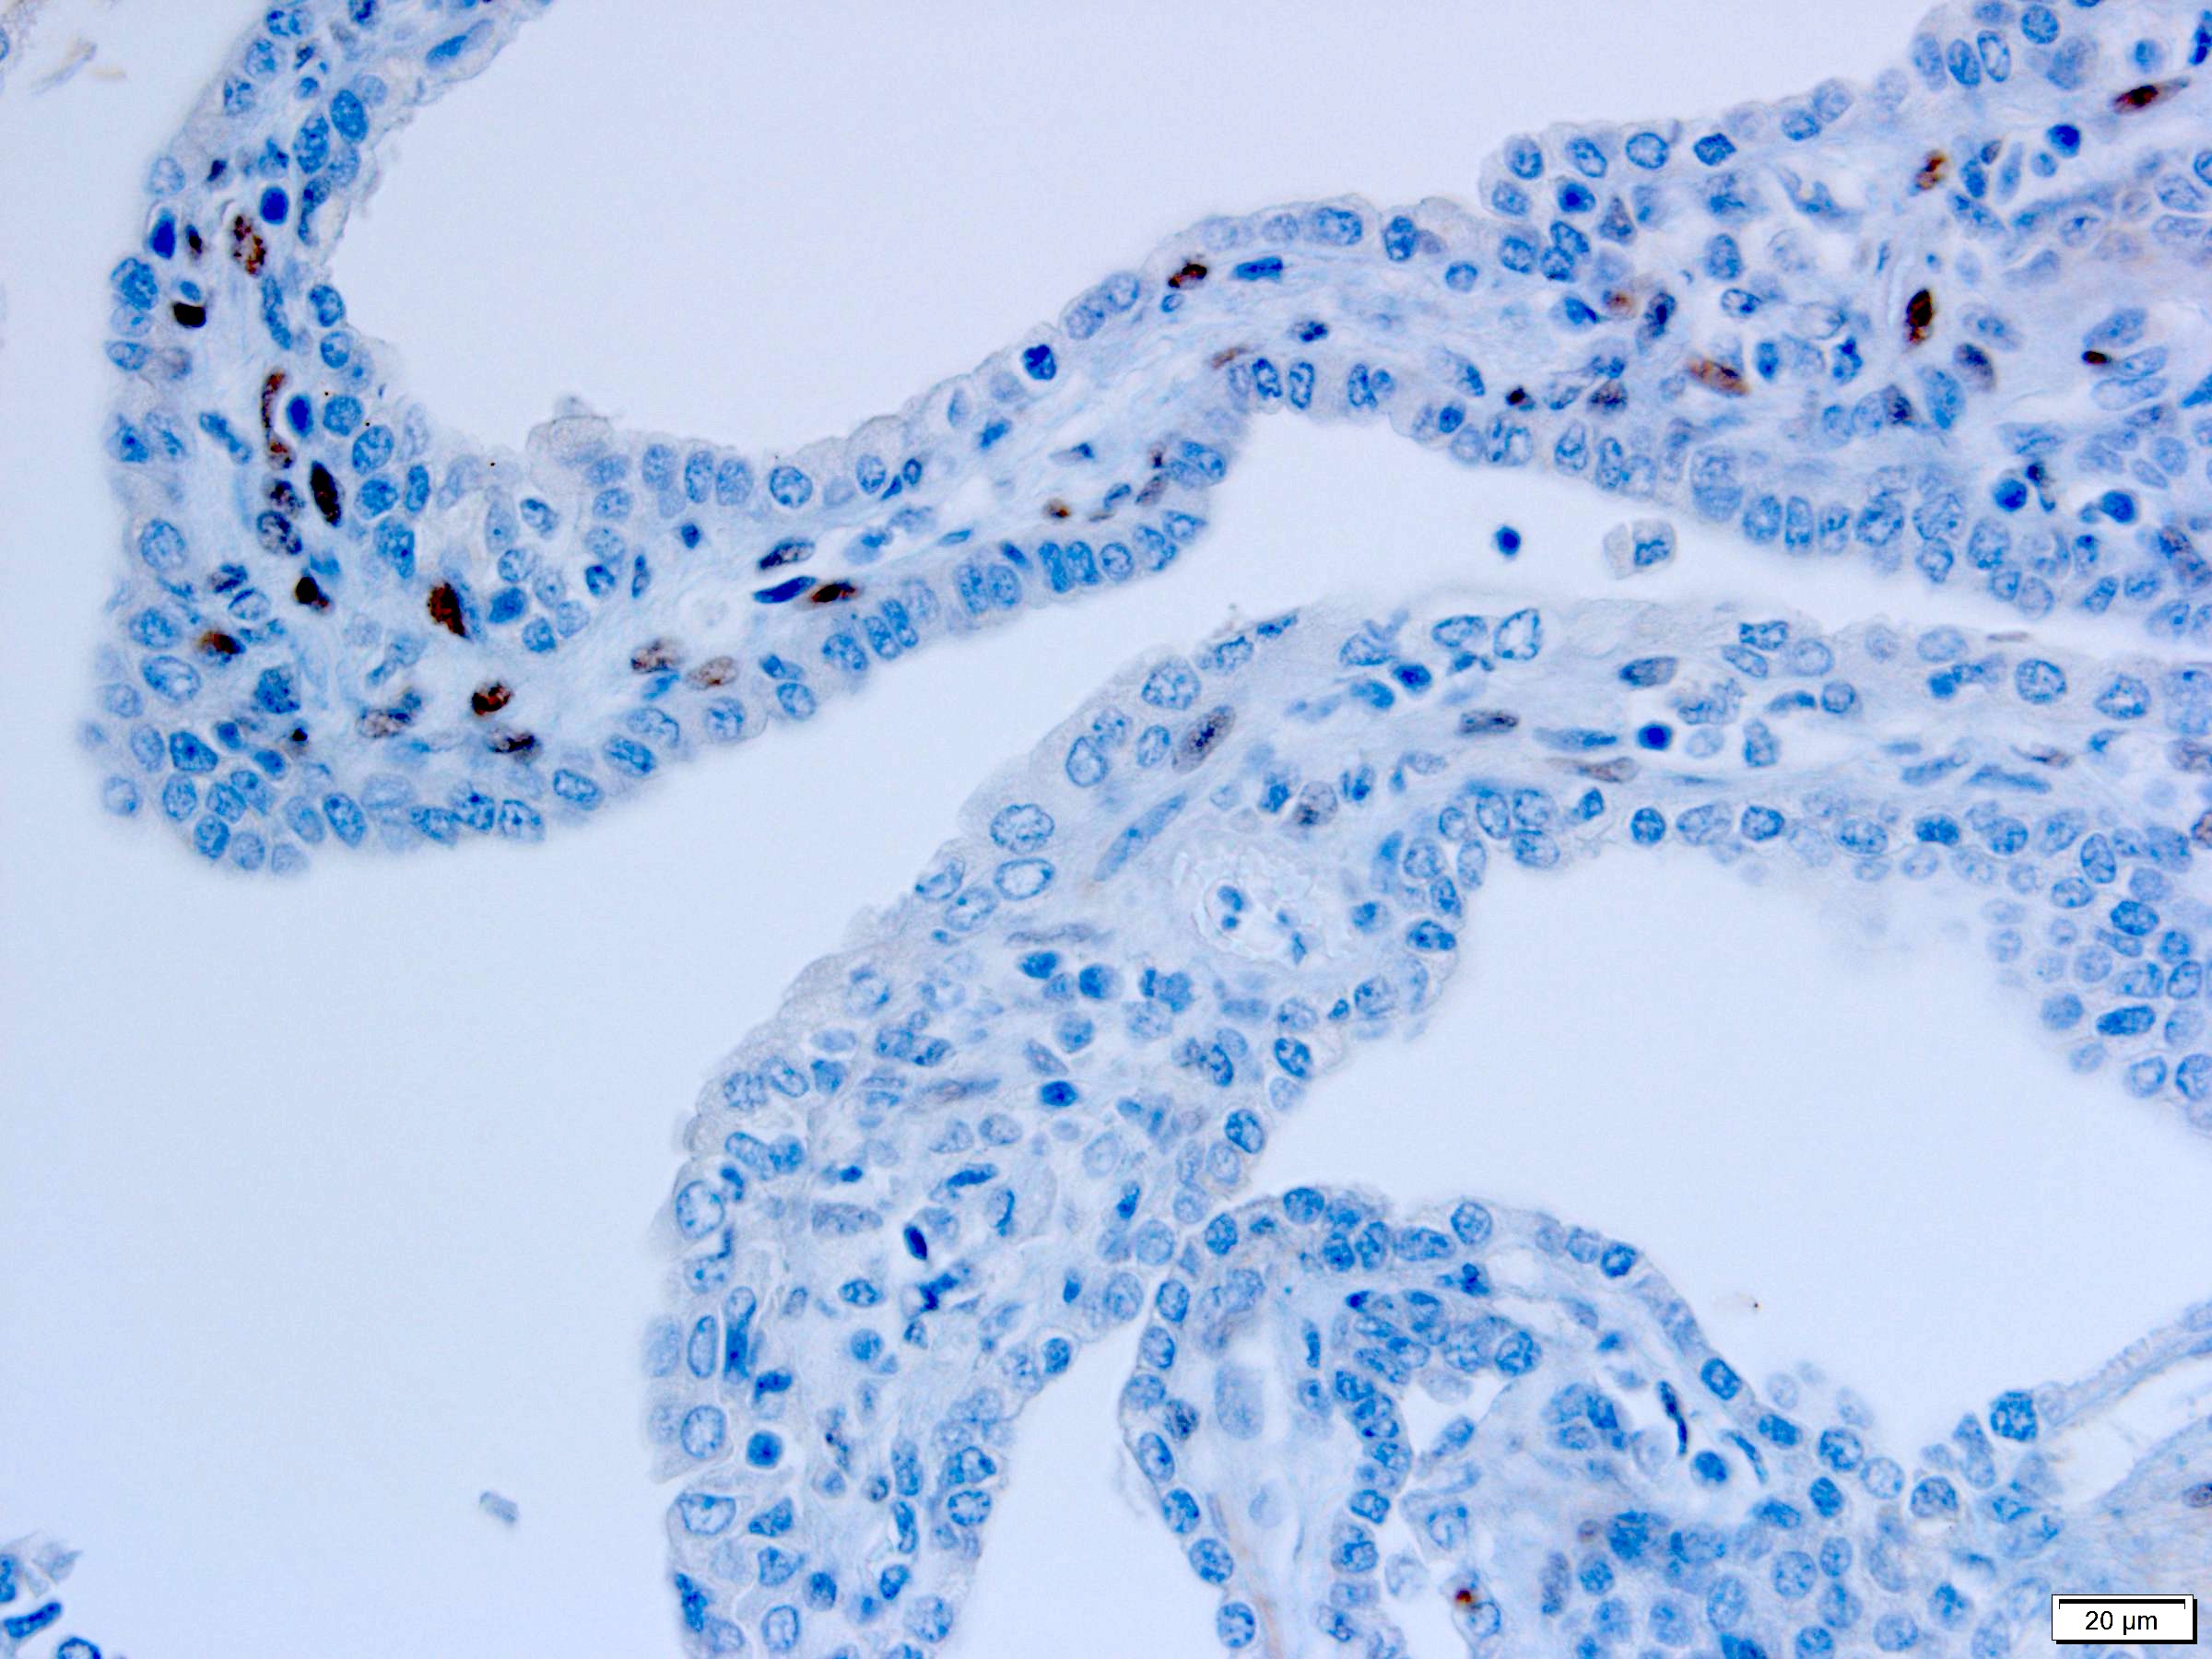

Positive stains

- Stroma:

- SMA: strong and diffuse, 95% (Am J Surg Pathol 2016;40:1591, Arch Pathol Lab Med 2004;128:1404, Arch Pathol Lab Med 2006;130:80)

- Desmin and caldesmon: more variable, 42% and 60%, respectively (Am J Surg Pathol 2016;40:1591, Arch Pathol Lab Med 2004;128:1404)

- ER and PR, 50% and 95%, respectively (Am J Surg Pathol 2016;40:1591, Arch Pathol Lab Med 2004;128:1404, Arch Pathol Lab Med 2006;130:80, Am J Surg Pathol 2007;31:489)

- CD10: mainly in spindle cells around epithelial elements, 81% (Am J Surg Pathol 2016;40:1591, Arch Pathol Lab Med 2004;128:1404, Am J Surg Pathol 2007;31:489)

- FOXL2: in ovarian type stroma, 90% (Hum Pathol 2014;45:1010)

- Comment: The sections show a well circumscribed tumor composed of multiple cysts lined by flattened or cuboidal epithelium. Immunohistochemistry was performed to show the septal stroma is positive for ER and PR. The morphologic and immunohistochemical findings support the diagnosis of adult cystic nephroma.

A 6 cm predominantly well circumscribed, multicystic mass was incidentally found in a 55 year old woman. Sections of the partial nephrectomy showed the above histologic features. The stromal component is positive for ER and PR (shown above). What is the likely diagnosis?

A. Adult cystic nephroma. Adult cystic nephroma is a well circumscribed, predominantly cystic mass. Angiomyolipoma with epithelial cysts shares overlapping histologic features but the stroma is immunopositive for melanocytic markers. Cystic partially differentiated nephroblastoma typically occurs in children. Multilocular cystic neoplasm of low malignant potential has nests of tumor cells with abundant clear cytoplasm and small nuclei without prominent nucleoli. None of the above choices, except for adult cystic nephroma, demonstrate immunoreactivity for ER and PR.